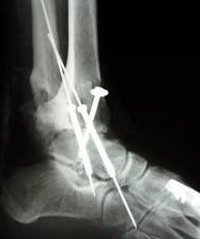

Остеосинтез таранной кости стопы выполняется при переломах таранной кости и переломах таранной кости с перемещением, если фрагменты не могут быть консервативно сопоставлены или сохранены, а также в случаях, когда закрытое сокращение может привести к дальнейшему разрушению кости. Тактическое вмешательство зависит от типа травматического повреждения. Винты или спицы используются для фиксации фрагментов. В послеоперационном периоде перед снятием швов их лечат в стационаре и подвергают дальнейшей реабилитации. Общая продолжительность иммобилизации составляет около 3 месяцев, инвалидность - около 4 месяцев.

Операция проводится в экстренном порядке под общим или проводящим наркозом. Выбор хирургического доступа к травматологии определяется в зависимости от типа перелома. В случае переломов шеи с подвывихом тела таранной кости в подтаранном суставе делают разрез вдоль передней поверхности голеностопного сустава с переходом на стопу. При переломах шейки матки с подвывихом тела таранной кости, медиально и сзади, делают разрез вдоль задней поверхности (за внутренней лодыжкой).

Место перелома обнажено, костные отломки выровнены и зафиксированы иглами или компрессионными винтами. Сшитая ткань, вшитая в кожу. Обездвижить пластик или гипс. Швы снимаются на 10-12 дней. Загрузка членства запрещена в течение трех месяцев. Затем допускается легкая нагрузка на ногу с использованием дополнительных опор (костылей). Трудоспособность восстанавливается через 3,5-4 месяца после травмы. В течение года после операции пациенту показывают ногу или ортопедическую обувь.